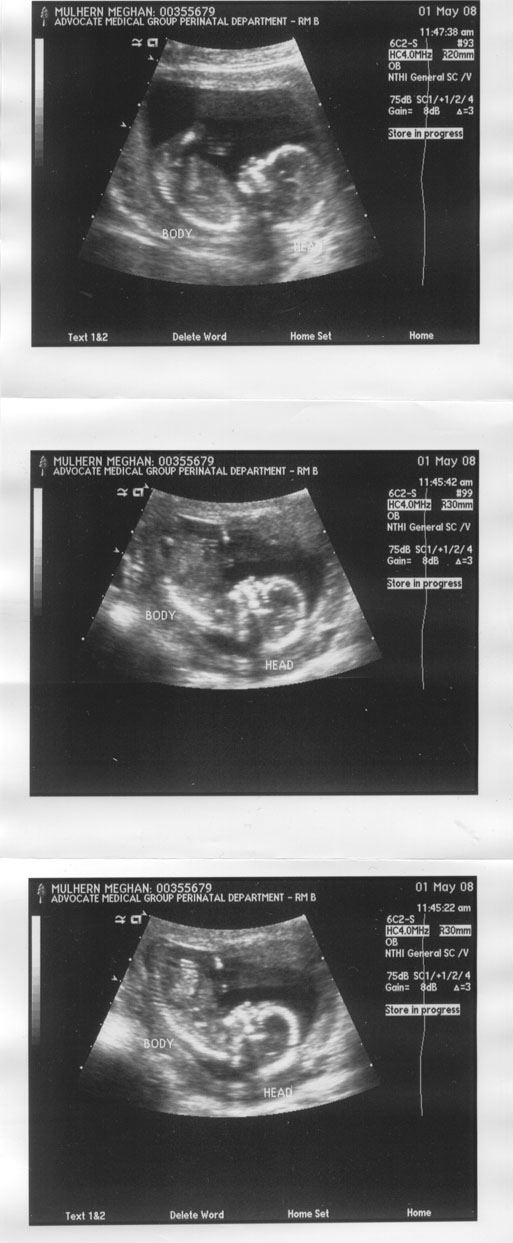

14 Week Ultrasound